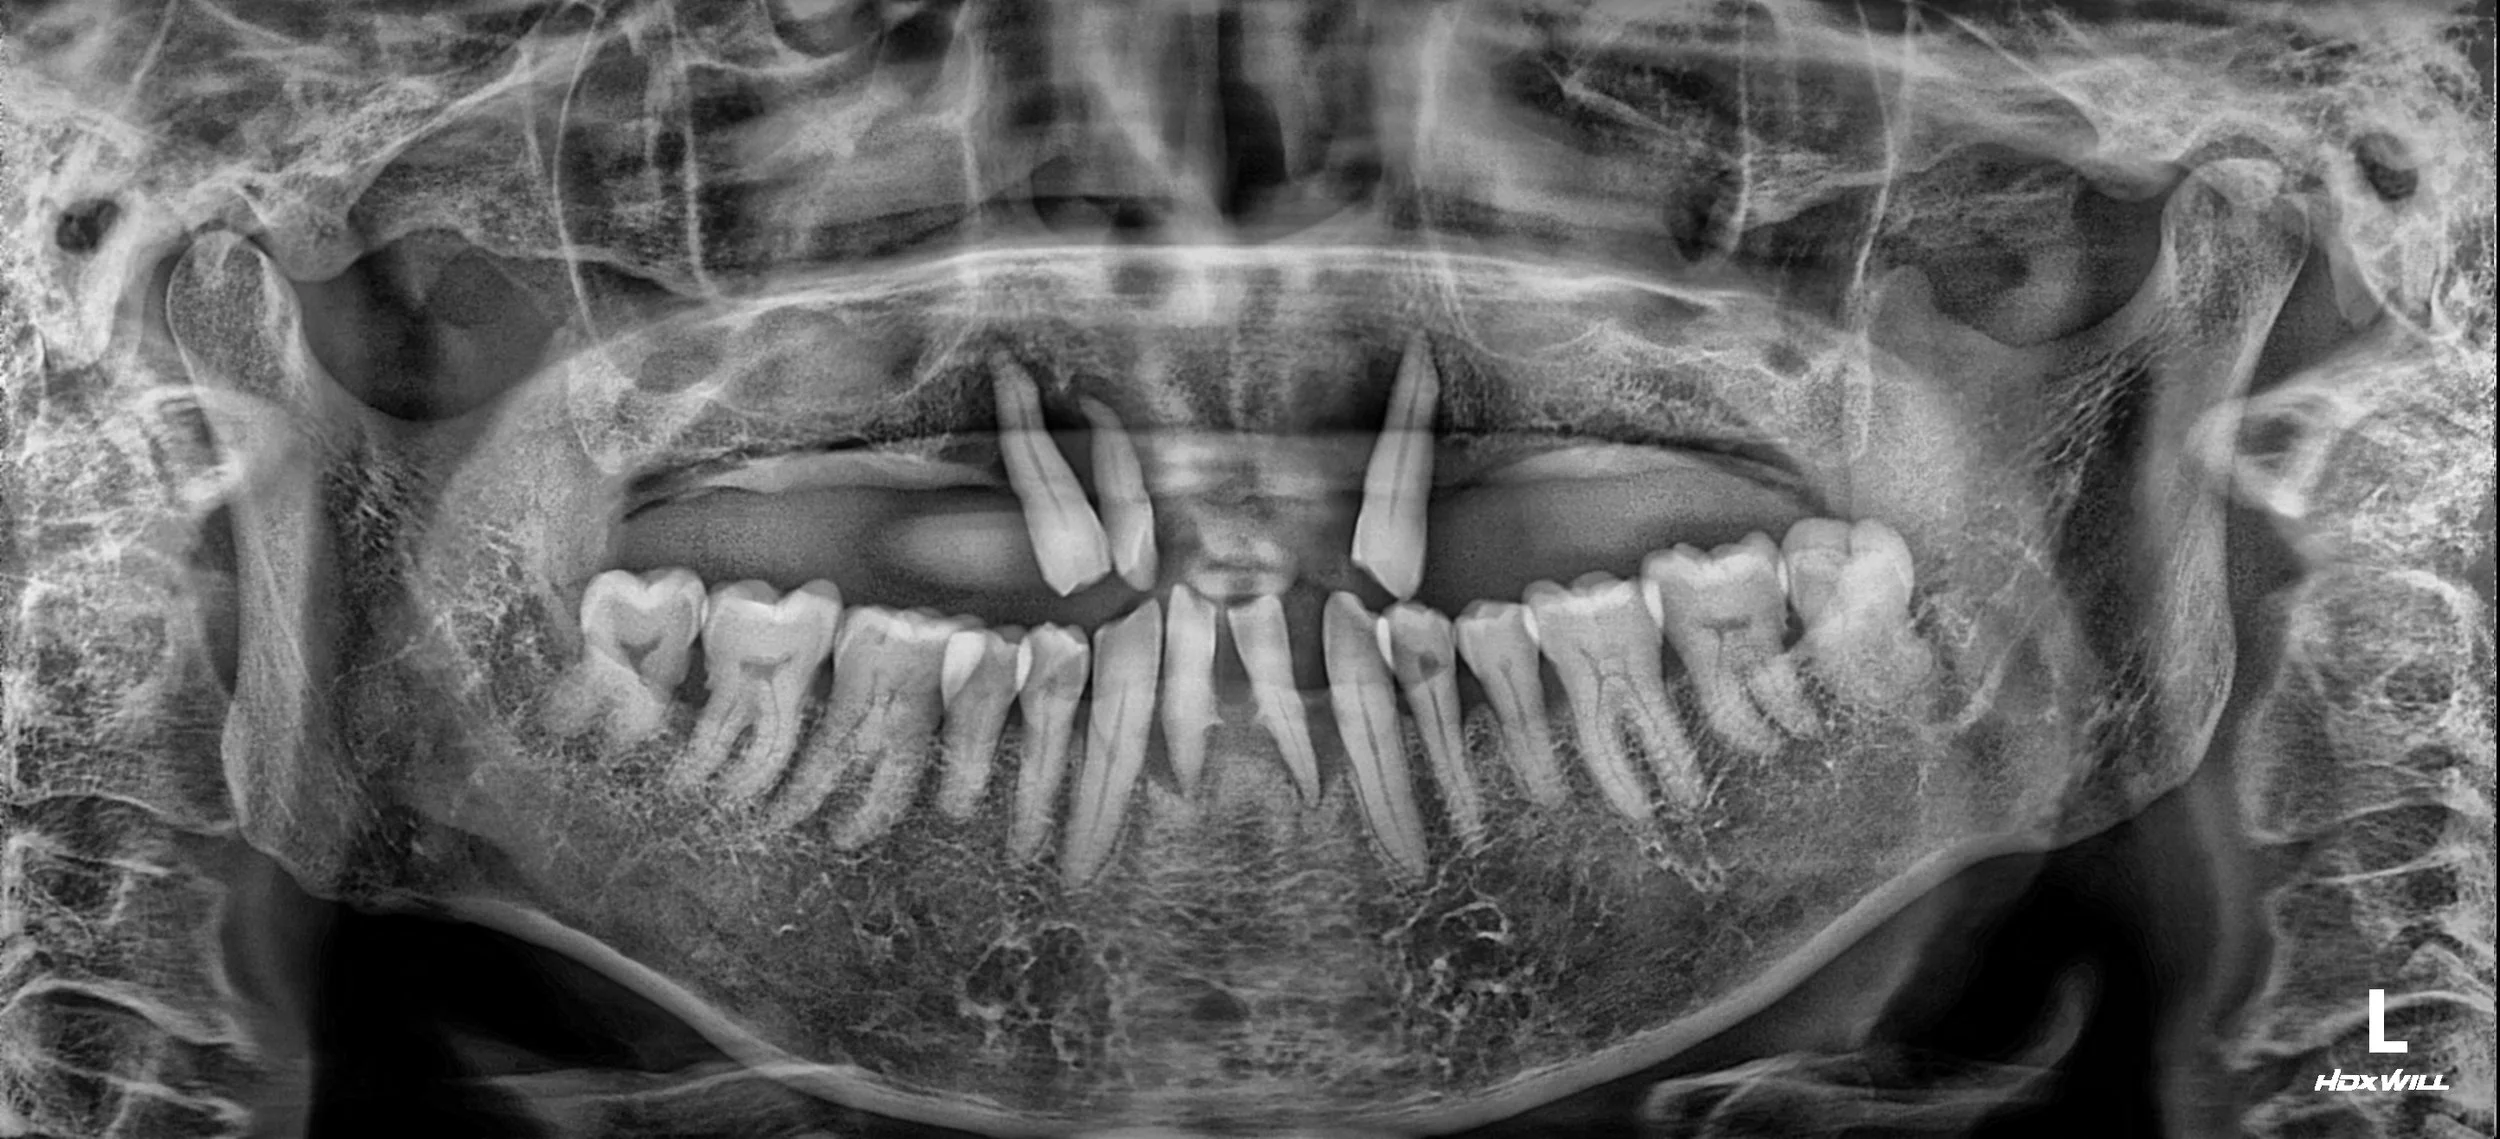

OPG - BEFORE